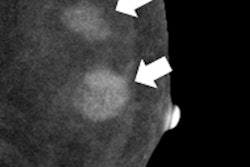

The study was approved by the German governmental Health Authorities and Ethics Committee, and included 68 patients with biopsy-proven breast cancer. Contrast-enhanced digital mammography was performed as a bilateral mammogram (Senographe DS, GE Healthcare), starting two minutes after injection of 1.5 mL/kg of an iodinated contrast agent (300 mg/mL) with a flow of 3 mL/sec. Contrast-enhanced digital mammography and mammography images were interpreted by three blinded independent radiologists with an interval of four weeks for memory washout.

The researchers found 23 false negatives in mammography. There were three false negatives in the combination (mammography plus contrast-enhanced mammography) and two false negatives in contrast-enhanced mammography alone. Sensitivity was 87.6 % for mammography, 97.4% for contrast-enhanced mammography, and 92.3% for the combination.

"Contrast-enhanced digital mammography alone showed equal detection and sensitivity for the index cancer than the combination with mammo," Fallenberg concluded. "It is superior to mammo alone in lesion detection, and there was no significant difference in size evaluation between all the three modalities. So I would say in symptomatic patients we can start with contrast-enhanced mammography alone upfront and save 50% of the radiation dose."